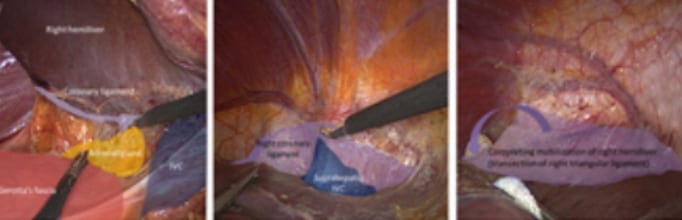

2. Semiprone offers a good view for right hemiliver mobilization

3. When the right hemiliver is mobilized, the right lobe slips to the left due to gravity and a large working space is created under the right side of the diaphragm. This large working space is in contrast to the small subphrenic space seen when a patient is positioned in supine position

Picture showing large tear in right hepatic vein. The patient was positioned in semiprone. CVP during parenchymal transection was 8. Although CVP was relatively high, blood loss was minimal giving the surgeon time to suture the venous tear.